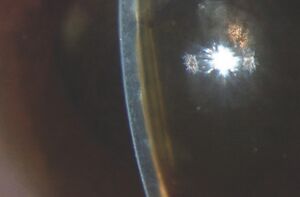

Patients often present with a red painful eye and decrease in vision. There is a higher incidence of malignant glaucoma in hyperopic eyes (short axial length). The intraocular pressure (IOP) is often very elevated but may present with “normal” or lower pressures leading to confusion about the diagnosis. Key to diagnosis is a flat chamber with both iris and lens positioned anteriorly and an almost flat anterior chamber (figure 1). The cornea shows signs of edema from both the elevated IOP as well as iris and lens touch. This should be distinguished from any post-operative swelling of the cornea. The opposite eye central anterior chamber is typically deep and this is one clue to distinguish malignant glaucoma from acute primary angle closure where the anterior chambers of both eyes are more symmetric. Ultrasound biomicroscopy can be useful in identifying anatomical structures when the corneal edema hinders slit lamp examination (figure 2). Optically clear “aqueous zones” have been described in the vitreous cavity although I have not seen this in my experience. History of intraocular surgery and laser should be explored including pars plana vitrectomy, trabeculectomy and the lasers mentioned earlier. Starting or stopping both cycloplegics as well as miotics have also been connected to the development of malignant glaucoma and should be part of the clinical history taking when possible.